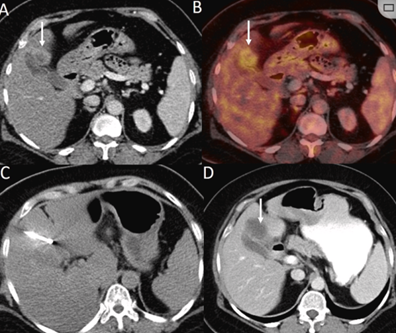

CT引導的冷凍消融

(b) 冷凍消融術(shù)中影像顯示冰球完全覆蓋病變。(c) 19個月后隨訪,沒有發(fā)生局部腫瘤進展。完全消融率為97%(66/68);2名患者均接受了額外的冷凍消融,隨后實現(xiàn)完全消融。平均隨訪期為 12.8 個月(范圍:3-27 個月)。所有患者均接受影像復查(CT 或 MRI)。11個病灶(16.2%)檢測到局部腫瘤進展,6、12和18個月時的累積局部腫瘤進展率分別為4%、8.2%和20.5%。8例出現(xiàn)遠處肝內(nèi)或肝外病變的患者接受經(jīng)動脈化療栓塞、經(jīng)動脈化療栓塞加射頻消融治療或全身化療。

( a ) 軸向 MRI 和 ( b ) 軸向 CT 顯示肝S8段有一個16mm的病灶,鄰近肝緣。( c )冷凍消融期間CT顯示放置了2個冷凍探針,低密度冰球包圍病灶。(d)術(shù)后1個月隨訪 CT顯示冰球?qū)?yīng)的壞死區(qū)域,未見復發(fā)。(e)術(shù)后6個月的CT,壞死區(qū)域縮小,未見復發(fā)。(f)與基線影像(g)相比,12個月后的FDG-PET/CT顯示未見FDG攝取。

62歲女性,肝轉(zhuǎn)移(卵巢癌)腫瘤的完全消融病例(a)軸向CT顯示病變位置毗鄰心臟和上腔靜脈(黑色箭頭)。(b)術(shù)中軸向CT掃描:使用三個冷凍探針。1個月后的軸向(e)和冠狀位(f)增強CT掃描顯示低密度區(qū)域,由于肉芽組織反應(yīng)引起的邊緣增強。